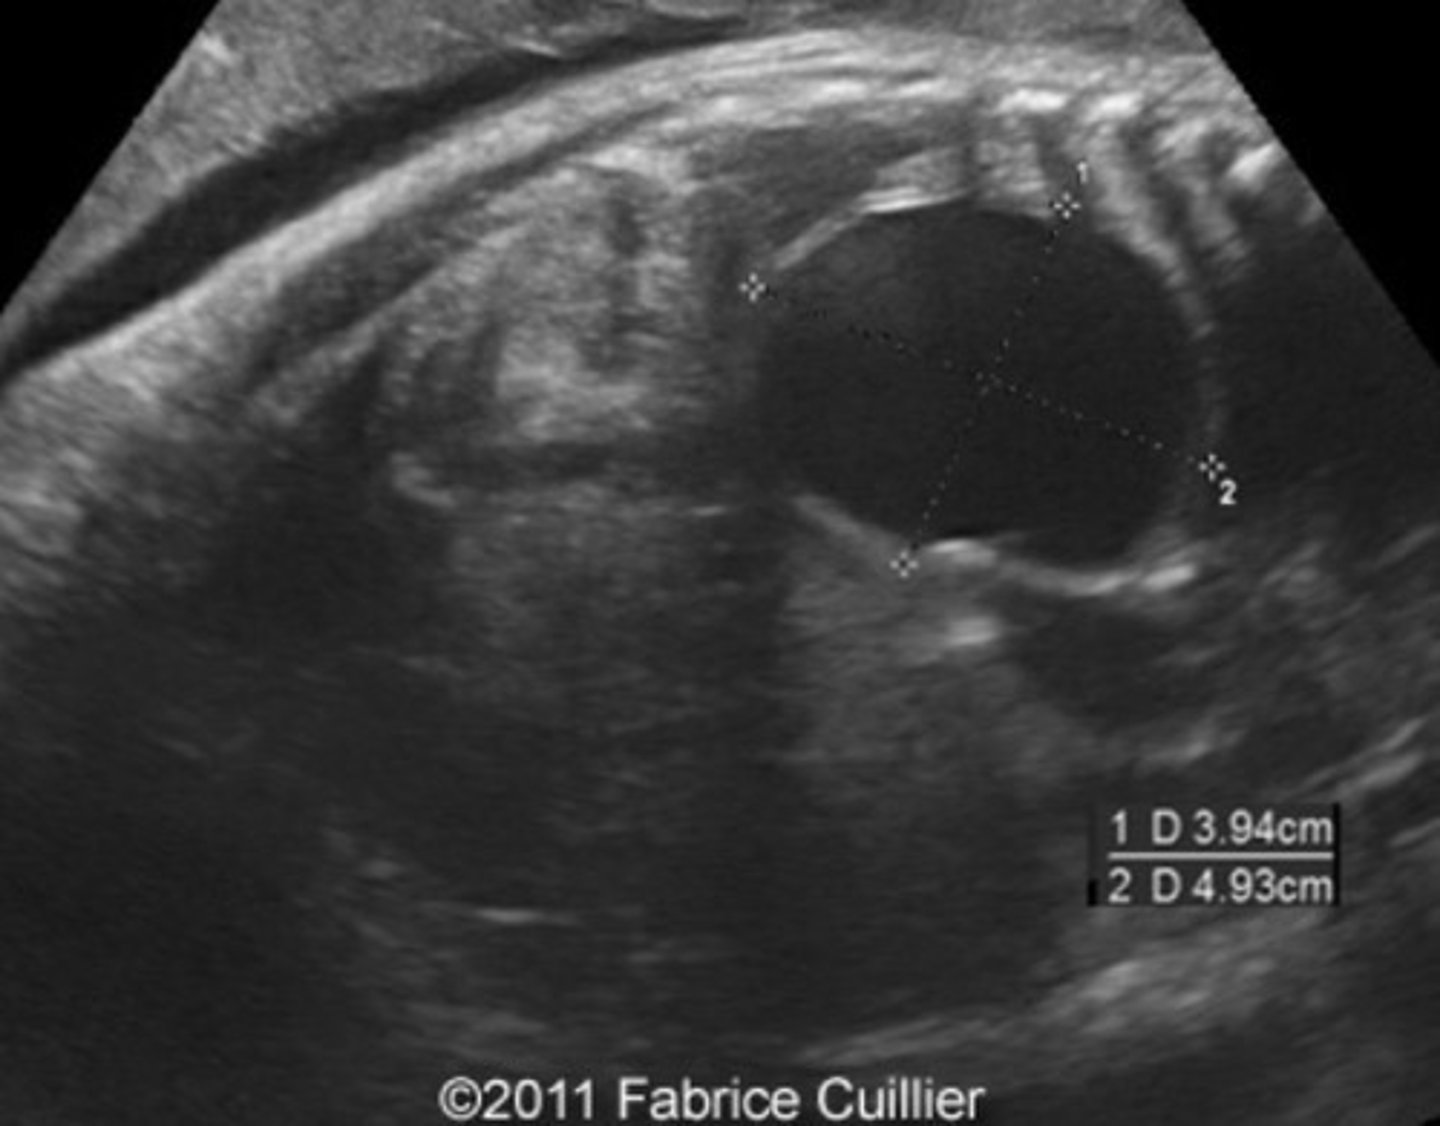

Potter's Syndrome Type II - Multicystic Dysplastic Kidney Disease

Kidney tissue is replaced by cysts - multiple and variable in size

Usually unilateral

Enlarged kidneys

Ill-defined walls & parenchyma/pelvis